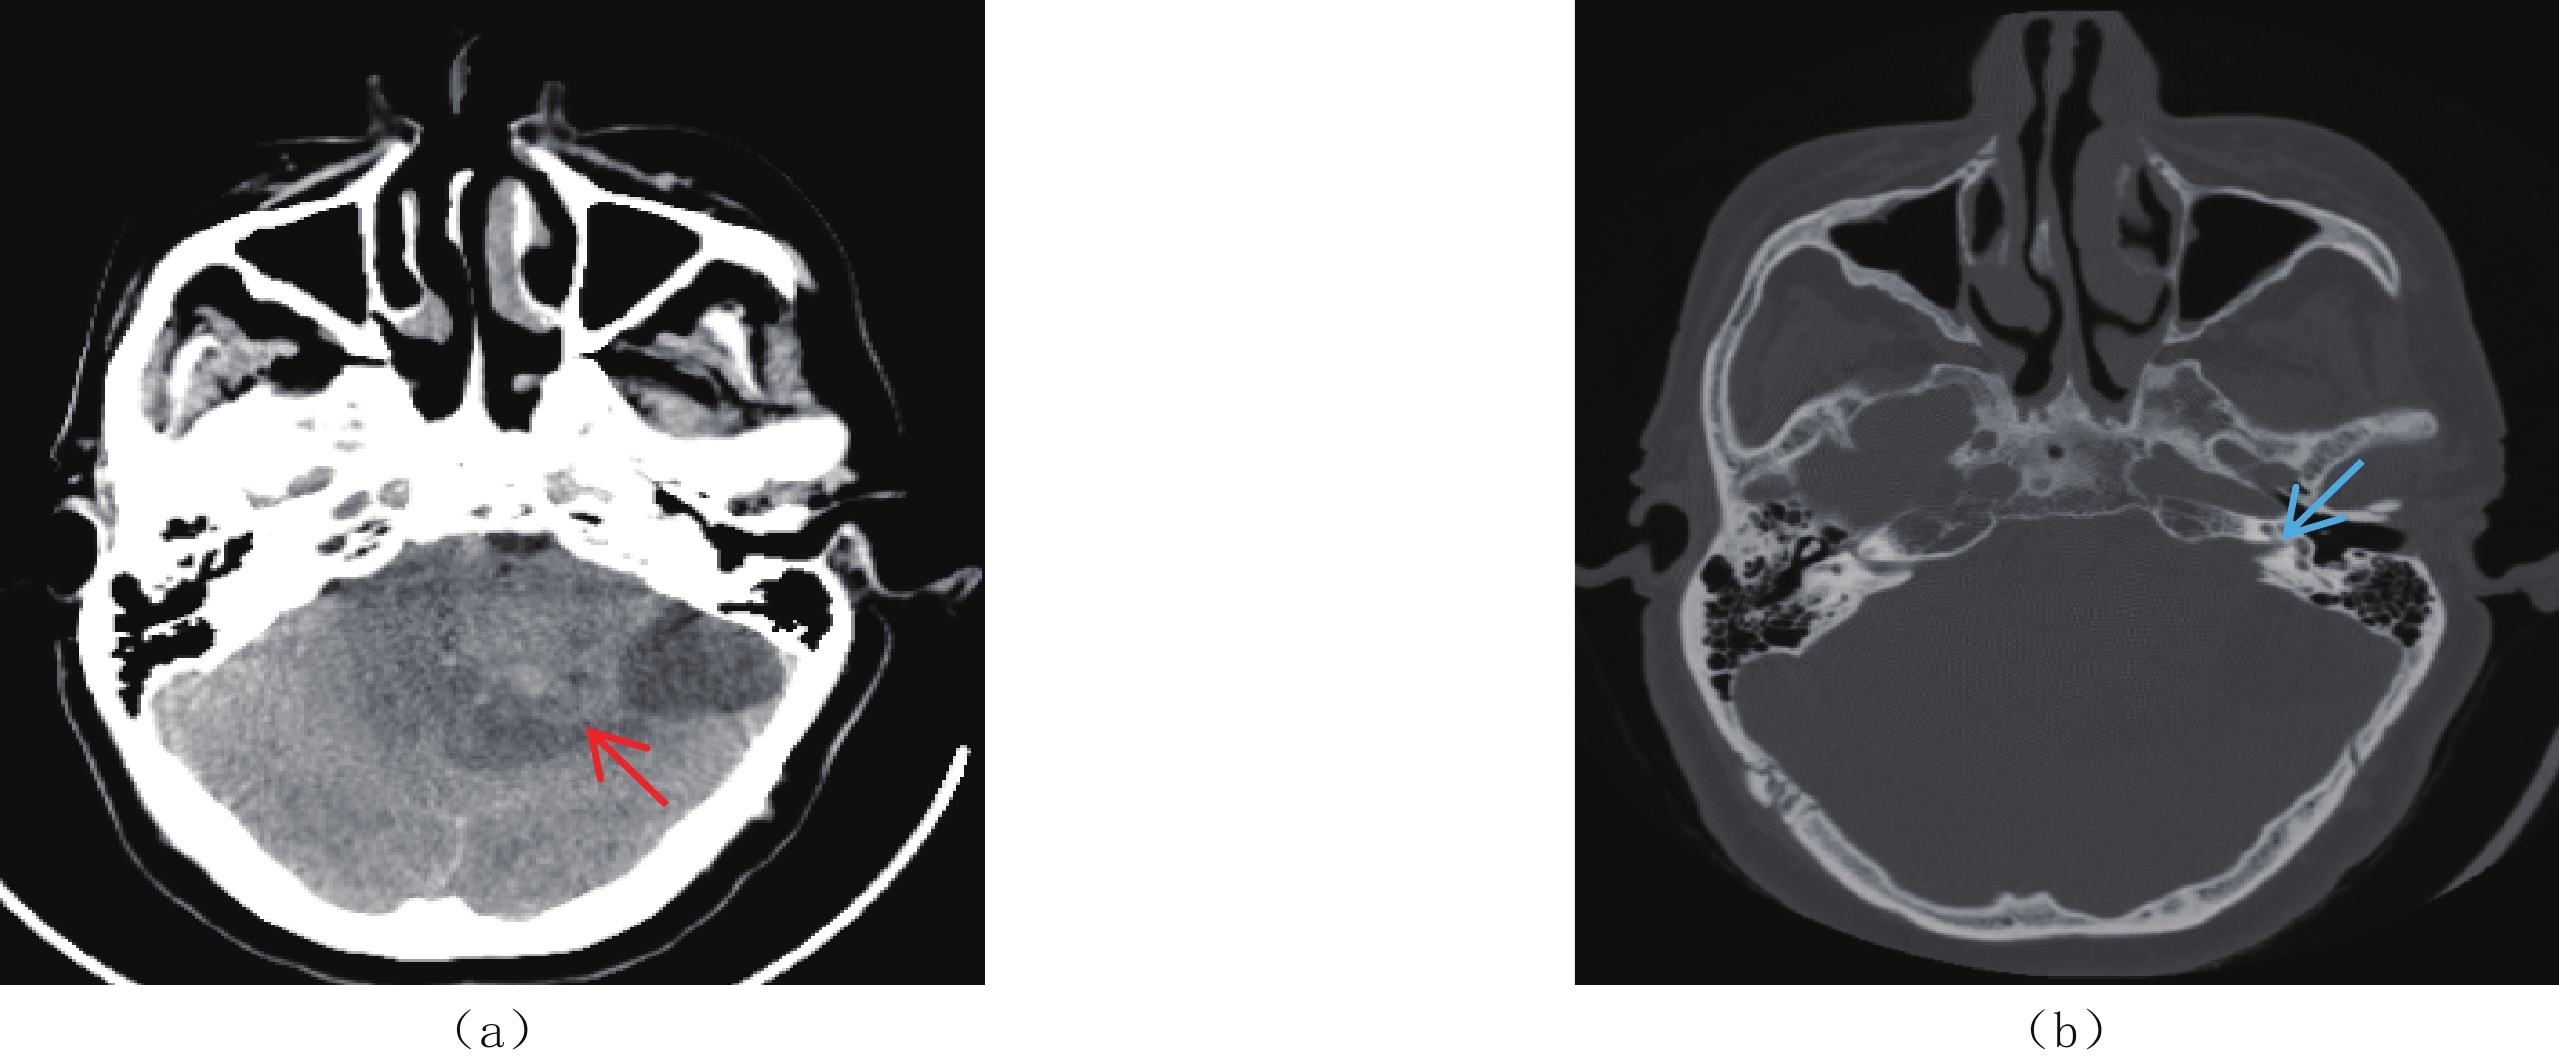

CT:平扫左侧桥小脑角区片状低密度影(图1)。MRI:左侧桥小脑角区听神经根部可见大小约4.3 cm×5.9 cm×4.8 cm,囊实性混杂信号影,实性部分T1WI、T2WI呈混杂信号,边界清晰,边缘欠规整,DWI呈混杂信号。增强扫描实性成分呈不均匀明显持续性强化(图2),听神经增粗,左侧内听道扩大。影像诊断为左侧听神经瘤。

![]() 图 2 ISFT患者MRI平扫及增强图像(a)~(c)MRI平扫示左侧桥小脑角区听神经根部大小约4.3 ㎝×5.9 ㎝×4.8 ㎝囊实性混杂信号影(红箭),实性部分T1WI(a)、T2WI(b)呈混杂信号,边界清晰,边缘欠规整,DWI(c)呈混杂信号,听神经增粗,左侧内听道扩大,邻近脑实质及第四脑室受压推移,瘤周水肿明显,并可见流空血管影;(d)~(g)增强扫描图像,(d)和(e)为轴位,(f)和(g)分别为矢状位和冠状位,肿瘤实性成分呈不均匀明显持续性强化(红箭),窄基底与硬脑膜相连,T2WI低信号区强化明显。Figure 2. MRI plain and contrast-enhanced images of the patient with ISFT

图 2 ISFT患者MRI平扫及增强图像(a)~(c)MRI平扫示左侧桥小脑角区听神经根部大小约4.3 ㎝×5.9 ㎝×4.8 ㎝囊实性混杂信号影(红箭),实性部分T1WI(a)、T2WI(b)呈混杂信号,边界清晰,边缘欠规整,DWI(c)呈混杂信号,听神经增粗,左侧内听道扩大,邻近脑实质及第四脑室受压推移,瘤周水肿明显,并可见流空血管影;(d)~(g)增强扫描图像,(d)和(e)为轴位,(f)和(g)分别为矢状位和冠状位,肿瘤实性成分呈不均匀明显持续性强化(红箭),窄基底与硬脑膜相连,T2WI低信号区强化明显。Figure 2. MRI plain and contrast-enhanced images of the patient with ISFT1.4 诊疗过程

CT平扫检查ISFT表现为孤立性、实质性肿块,多呈圆形、类圆形,一般体积较大,边界多光整,境界清楚,无分叶或浅分叶,呈软组织密度,囊变坏死区呈低密度,钙化少见。增强扫描病灶实性部分明显强化,体积较大时可见无强化的囊变坏死区[6]。

MRI检查具有良好的软组织分辨能力,在ISFT诊断中具有明显优势。T1WI多呈等低或等信号,T2WI可表现为高信号、稍高信号或低信号。T2WI上出现高低信号混杂的现象称为“阴阳征”或“黑白征”,是影像诊断ISFT一个相当重要的典型征象,即高信号区反映黏液坏死变性及血管间质细胞堆积,稍高信号区反映肿瘤细胞密集区域,低信号区反映致密胶原纤维[7-8]。动态增强扫描肿瘤多为不均匀持续性强化或进行性延迟强化,T2WI低信号区明显强化[9-10]。

此外,ISFT由于瘤体及瘤周血运丰富,常出现流空血管影,也是典型征象之一。但是部分脑膜瘤也可见血管流空,区别在于ISFT多表现为“蛇形流空效应”,而脑膜瘤以“光芒征”多见,其原因是ISFT主要来源于颈内动脉或椎动脉分支供血,而脑膜瘤主要来源于颈外动脉的脑膜中动脉供血[11-12],因此可以为二者鉴别诊断提供思路。部分ISFT可见“脑膜尾征”,但该征象少见,不具有特异性,只能说明肿瘤与硬脑膜关系密切,并不能对肿瘤来源进行鉴别。

本例患者出现“阴阳征”与流空血管影,并且肿瘤以窄基底与硬膜相连,呈“脑膜尾征”,符合文献报道。

图 2 ISFT患者MRI平扫及增强图像

(a)~(c)MRI平扫示左侧桥小脑角区听神经根部大小约4.3 ㎝×5.9 ㎝×4.8 ㎝囊实性混杂信号影(红箭),实性部分T1WI(a)、T2WI(b)呈混杂信号,边界清晰,边缘欠规整,DWI(c)呈混杂信号,听神经增粗,左侧内听道扩大,邻近脑实质及第四脑室受压推移,瘤周水肿明显,并可见流空血管影;(d)~(g)增强扫描图像,(d)和(e)为轴位,(f)和(g)分别为矢状位和冠状位,肿瘤实性成分呈不均匀明显持续性强化(红箭),窄基底与硬脑膜相连,T2WI低信号区强化明显。

Figure 2. MRI plain and contrast-enhanced images of the patient with ISFT